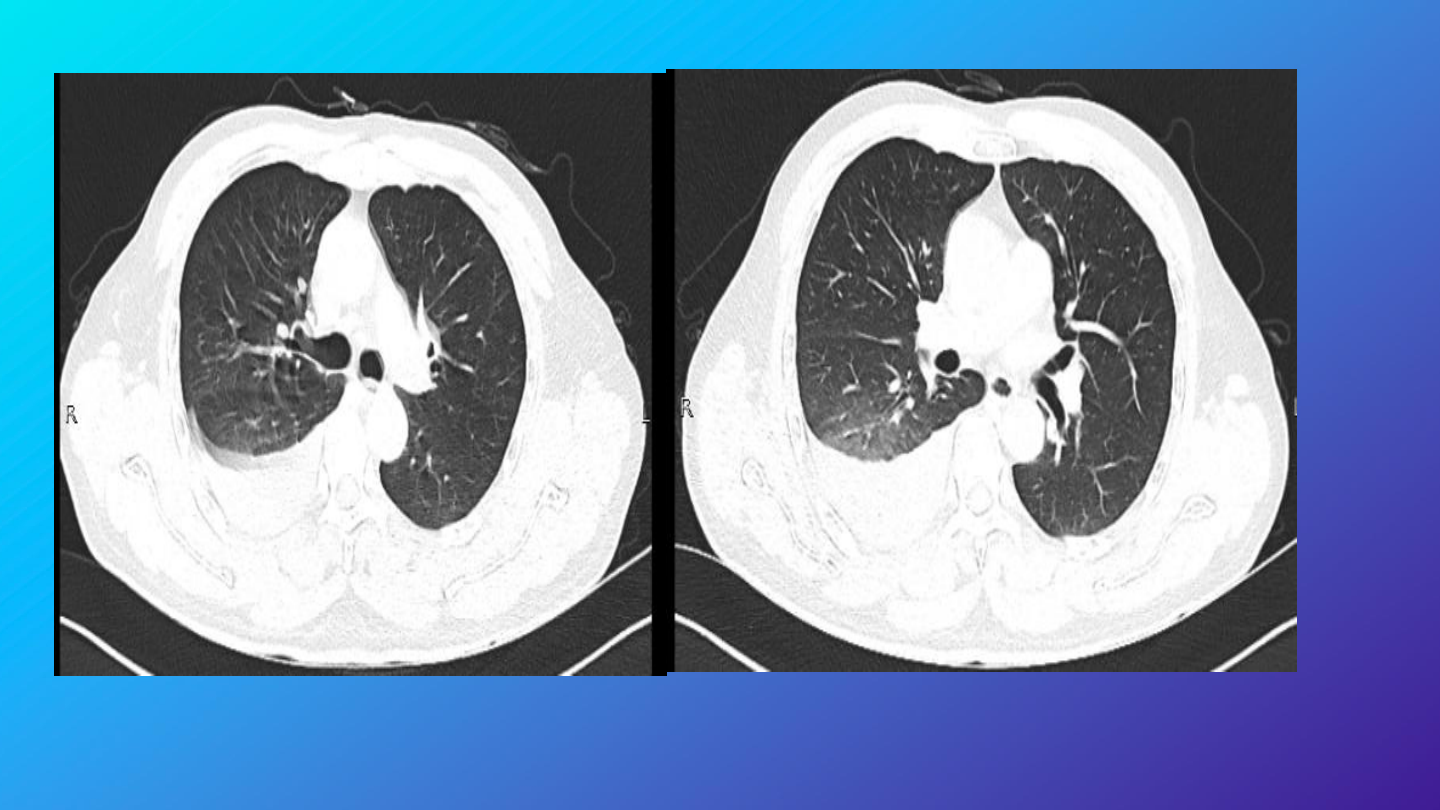

急诊完善胸腹部

CT

检查

结果:

右肺中下叶及左肺下叶炎性渗出,右侧胸腔

积液,建议治疗后复查。

左肺各叶数枚良性小结节及钙化灶。

右侧第

6

肋骨骨皮质褶皱。

肝内数枚囊肿。右侧腹股沟管增宽,部分脂

肪疝出。